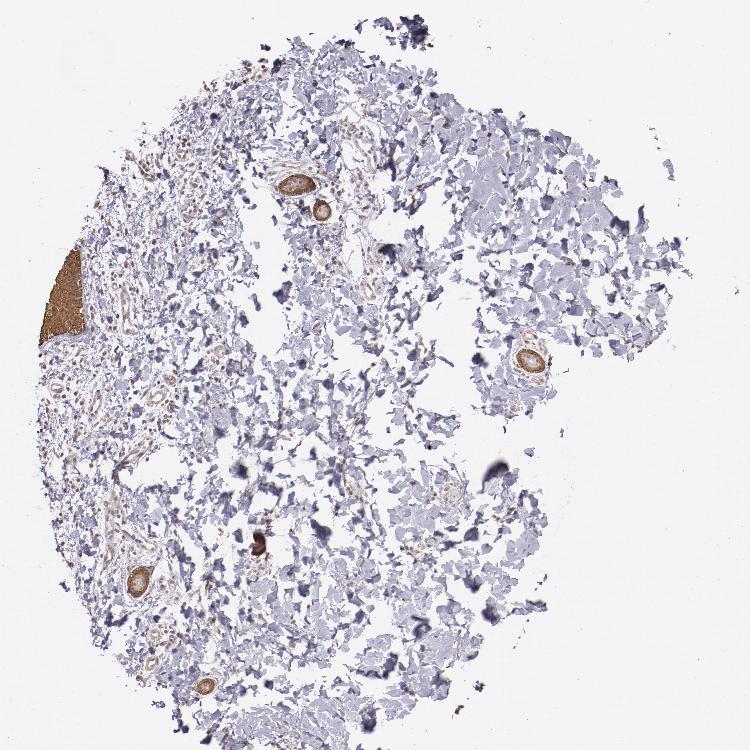

SKIN 2 - Antibody stainingi

Antibody staining in the annotated cell types in the current human tissue is reported as not detected, low, medium, or high, based on conventional immunohistochemistry profiling in selected tissues. This score is based on the combination of the staining intensity and fraction of stained cells.

Each image is clickable and will lead to virtual microscopy that enables deeper exploration of all samples and also displays staining intensity scores, fraction scores and subcellular localization as well as patient and tissue information for each sample.

Antibody HPA001755Antibody CAB005172

Epidermal cells HighMedium